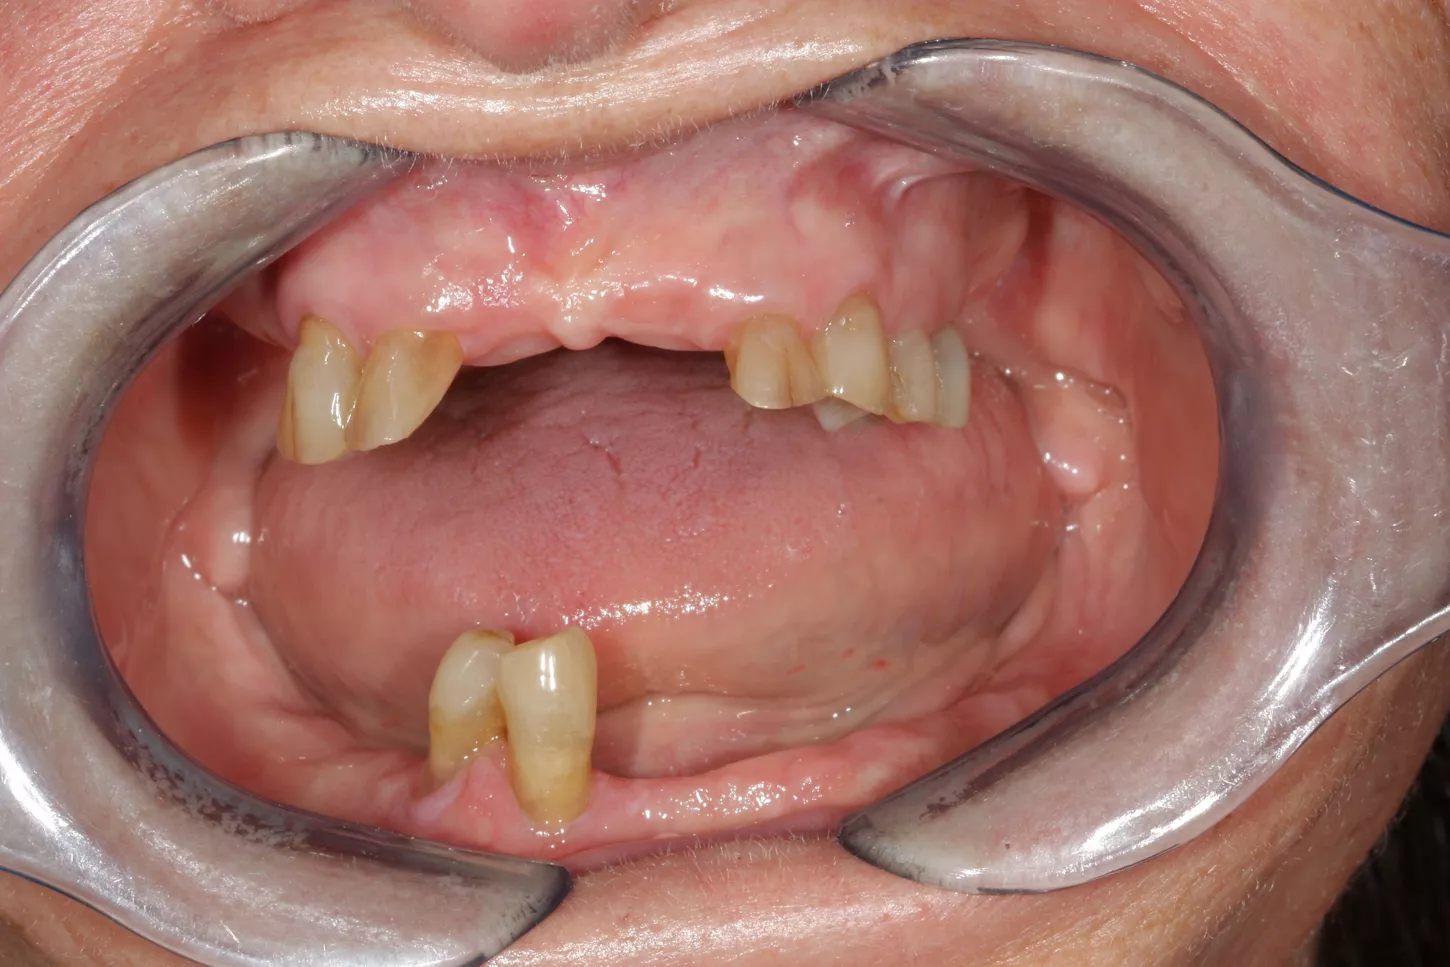

Clinical examination with x-ray showing a poor prospective for long-term prosthetic life of teeth on the lower jaw. In the upper jaw, teeth 13, 12, 22, 23, 24 and 25 were permanently preserved following preliminary treatment.

2. Display of teeth once pretreatment was completed. Treatment plan for the implant positions done using CBCT and intraoral scans at this stage.